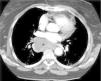

Masa cervical y mediastínica en una mujer de 72 años